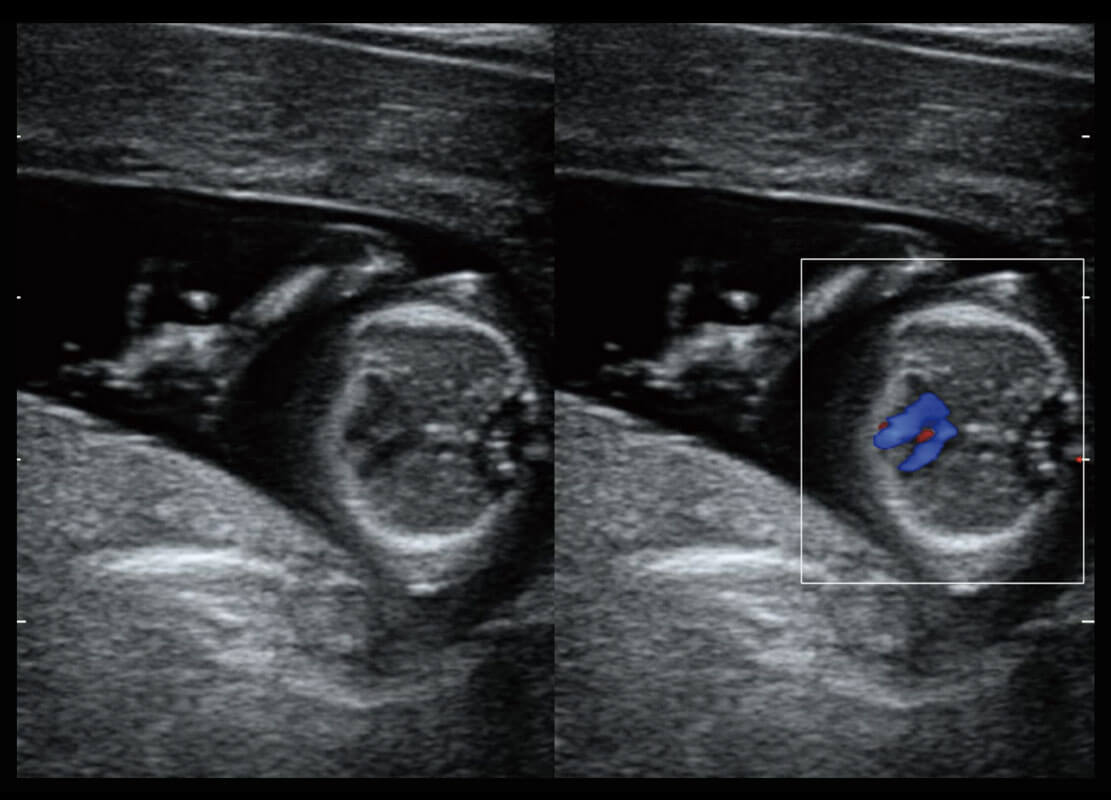

P60搭载一系列胎儿心脏成像技术,实现精细的胎儿心脏评估。

四腔切面

四腔心血流

右室双出口

胎心容积成像